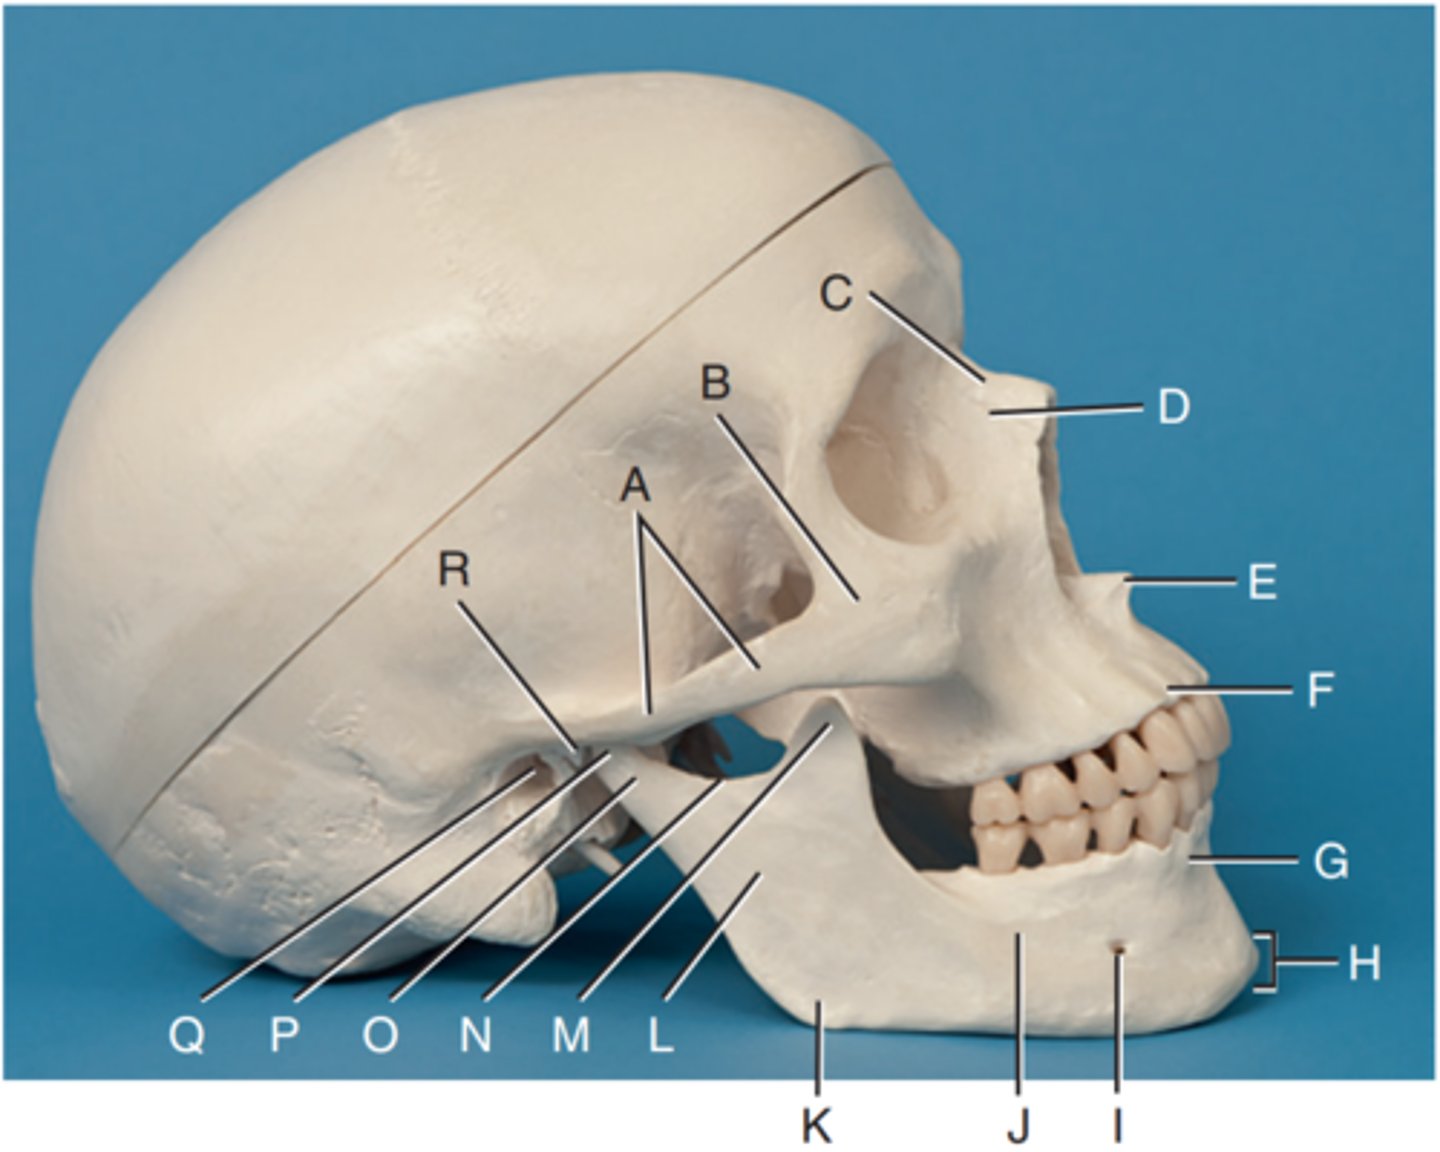

Zygomatic arch

Label A

Right zygomatic bone

Label B

Right nasal bone

Label C

Frontal process of right maxilla

Label D

Anterior nasal spine

Label E

Alveolar process of maxilla

Label F

Alveolar process of mandible

Label G

Mentum or mental protuberance

Label H

Mental foramen

Label I

Body of mandible

Label J

Angle (gonion)

Label K

Ramus of mandible

Label L

Coronoid process

Label M

Mandibular notch

Label N

Neck of mandibular condyle

Label o

Condyle or head of mandible

Label P

EAM

Label Q

TM fossa of temporal bone

Label R

Greater wings of sphenoid

Label S

Lesser wings of sphenoid with anterior clinoid processes

Label T

Ethmoid sinuses between orbits

Label U

Body of maxilla containing maxillary sunuses

Label V